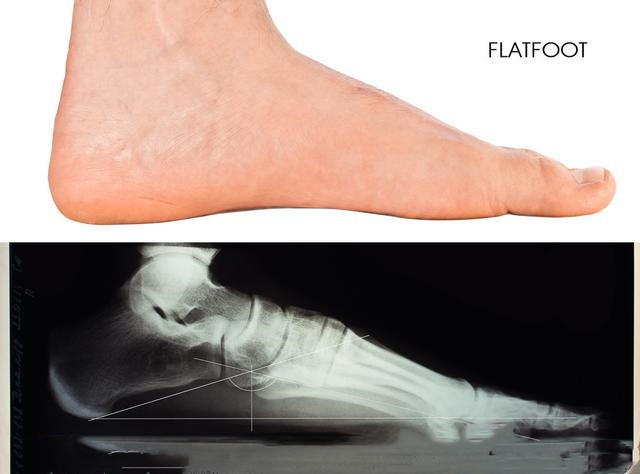

一、 先来了解下什么是“扁平足”

如何判断自己是不是扁平足呢?其实很简单,把鞋子脱了以后光脚站在地上,如果整个脚底都贴在地面上,那你就是典型的扁平足了。再一个就是从侧面观察自己的脚底,正常人的脚是有明显的弯曲的足弓的,而扁平足则是一条直线。

结构性扁平足又称为刚性扁平足,所谓刚性就是说无论是站着还是坐下都没有足弓。这种扁平足是真的平,多发生在胫骨后肌肌腱功能障碍患者的身上,不一定是两只脚同时患有,也可能只存在于一只上。这种扁平足是由骨骼发育畸形造成的,常伴随有疼痛感,极难修复。